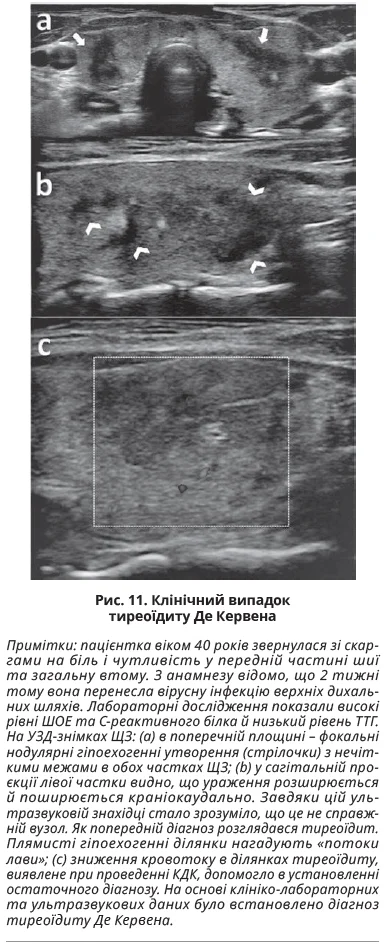

Підгострий тиреоїдит Де Кервена виникає внаслідок імунної відповіді після перенесеної вірусної інфекції або інфекції верхніх дихальних шляхів. Для клінічної картини тиреоїдиту Де Кервена характерні гострий біль у шиї, болісний на дотик зоб і системні симптоми, як-от лихоманка, втомлюваність, дисфагія, втрата ваги, високі рівні ШОЕ або С-реактивного білка, зниження ТТГ. У гострій фазі захворювання може спостерігатися гіпертиреоз, який зазвичай змінюється гіпотиреозом тривалістю 6-18 місяців, після чого пацієнти повертаються до еутиреоїдного стану. Типова ультразвукова картина ЩЗ характеризується наявністю неоднорідних, нечітко окреслених гіпоехогенних ділянок зі зниженим кровотоком в одній або обох частках із залученням тиреоїдної паренхіми. Іноді картину описують як «лавовий потік» із дифузними та злитими гіпоехогенними ділянками. Отже, в гострій фазі тиреоїдиту Де Кервена на УЗД-знімках можна побачити гіперваскуляризацію ЩЗ, тоді як для підгострої фази характерна дифузна гіповаскуляризація залози. Випадок підгострого гранулематозного тиреоїдиту представлено на рисунку 11.